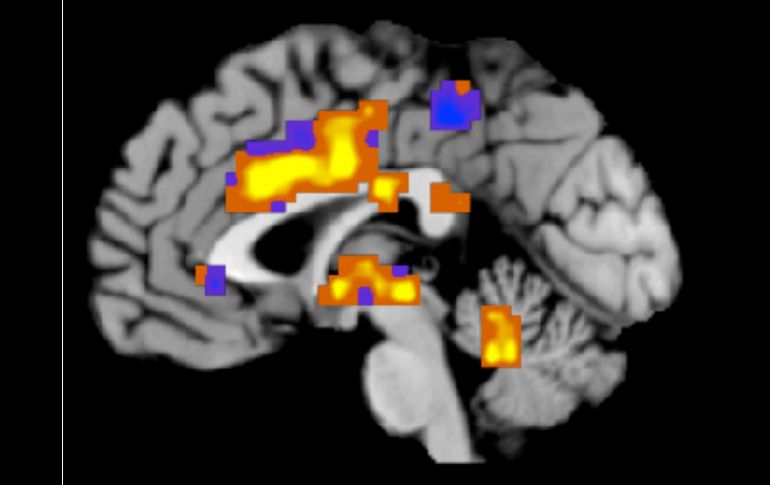

Tecnología | Aplican los estímulos sobre el cuero cabelludo de los pacientes Atacan la epilepsia con impulsos eléctricos Aplican los estímulos sobre el cuero cabelludo de los pacientes como una opción efectiva en la reducción de crisis Por: NTX 23 de mayo de 2013 - 19:08 hs Explican que aún es necesario hacer diversas pruebas para asegurar que no haya efectos secundarios adversos. ARCHIVO / CIUDAD DE MÉXICO (23/MAY/2013).- Impulsos eléctricos sobre el cuero cabelludo de los pacientes con epilepsia parece ser una opción efectiva en la reducción de crisis y sin efectos secundarios adversos, según resultados preliminares de laboratorio, afirmó la investigadora Luisa Lilia Rocha Arrieta. La científica del Departamento de Farmacobiología, adscrita al Centro de Investigación y de Estudios Avanzados (Cinvestav), señaló que su equipo está colaborando con expertos de la Universidad de Rhode Island, en Estados Unidos, en particular con el ingeniero en bioelectrónica, Walter Besio, para diseñar electrodos con ese fin. Explicó que han encontrado que ese tipo de estimulación en animales reduce la excitabilidad del cerebro, por lo que intentan encontrar un tipo de estimulación que sea accesible a cualquier tipo de persona que no requiera la introducción a nivel intracerebral de electrodos o la estimulación del nervio vago que implica una cirugía. En vísperas del Día Mundial de la Epilepsia, a celebrarse este 24 de mayo, dijo que según el Programa Prioritario de Epilepsia del Sector Salud, casi dos millones de mexicanos padecen este trastorno, siendo la causa más frecuente la cisticercosis (larvas de taenia solium, conocida como solitaria, instaladas en el sistema nervioso central). Explicó que aún es necesario hacer diversas pruebas para asegurar que no haya efectos secundarios adversos peores que la misma crisis, ya que si este tipo de estimulación causara demasiada supresión de la actividad cerebral, podría derivar en padecimientos como la depresión. La doctora en Farmacología reconoció que en décadas pocos han sido los cambios en el tratamiento, porque aunque existen diversas drogas antiepilépticas, en la mayoría de los casos los pacientes tardan en acudir al médico o toman medicamentos de manera arbitraria, lo que provoca que el cerebro se vuelva resistente a fármacos antiepilépticos. Otra estrategia ha sido la cirugía de epilepsia, pero no todos los pacientes son candidatos, pues se necesita una evaluación integral e investigación exhaustiva sobre sus posibles consecuencias para asegurar que una vez que se remueva el foco epiléptico no se afecte la memoria o el movimiento de alguna parte del cuerpo del paciente. Para la ganadora del premio a los 30 Personajes que Transforman a México en la categoría de Conciencia (Neuropsicología), otorgado por la revista Quo y Discovery Channel, los altos costos en los tratamientos han provocado que la gente recurra a curanderos o a la medicina alternativa. "Aquí la cuestión es tener conocimiento de que la epilepsia no es una, sino muchas y cada tipo de epilepsia requiere un tratamiento específico. Estamos en el siglo XXI y las personas le siguen teniendo miedo a la palabra epilepsia. "Eso produce una estigmatización muy fuerte, casi como la que se vivía en la época medieval en la que hablar de epilepsia era hablar del demonio en el cuerpo de las personas que lo padecen y no es así", puntualizó. Temas Ciencia médica Epilepsia Cerebro Lee También Julieta Fierro será homenajeada en la FIL INAPAM: ¿Cómo solicitar un turno para consulta médica gratuita? Nobel de Química premia el desarrollo de estructuras metal-orgánicas Nobel de Física para Clarke, Devoret y Martinis por descubrimiento sobre fenómenos cuánticos Recibe las últimas noticias en tu e-mail Todo lo que necesitas saber para comenzar tu día Registrarse implica aceptar los Términos y Condiciones